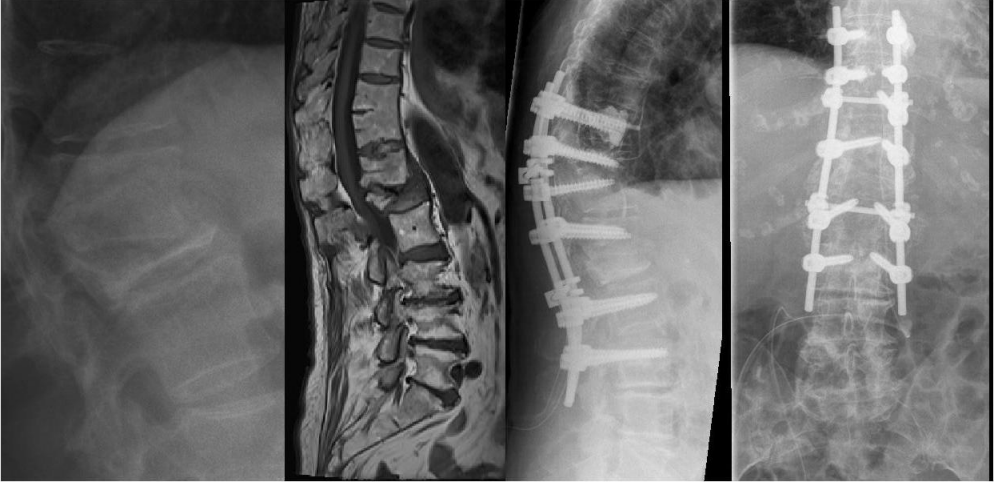

An 84-year-old female patient underwent surgery, due to a progressive kyphotic deformity and spinal cord compression after L1 fracture in severe osteoporosis 8 weeks ago. She was moved to hospital with extended wound necrosis and exogenous vertebral infection after long segment posterior stabilization. The critical soft tissue conditions and septic pedicle screw loosening required a complete implant removal. Because of the large decompression zone, an external spine fixation was necessary to ensure stability. Repetitive surgical debridement, local and systemic antibiotics and vacuum closure therapy led to soft tissue recovery and CRP normalization. The definitive internal stabilization and wound closure occurred after 4 weeks (Figure 8 [Fig. 8], Figure 9 [Fig. 9], Figure 10 [Fig. 10], Figure 11 [Fig. 11], Figure 12 [Fig. 12], Figure 13 [Fig. 13], Figure 14 [Fig. 14]).

Figure 8: L1 compression fracture in severe osteoporosis led to kyphosis and spinal cord compression. Long segment posterior stabilization and multilevel decompression.

Figure 9: The sagittal CT image reveals the extent of the posterior instability.

Figure 11. Left: Complete implant removal, radically surgical debridement and external spine fixation with vacuum wound closure (Hoffmann II external fixator, 5.0 mm Pins). Right: X-ray Image of the thoracolumbar spine. External posterior stabilization.

Figure 14: X-ray image of the final internal posterior stabilization (Longitude, Medtronic; cement-augmented pedicle screws, 7.5 mm)